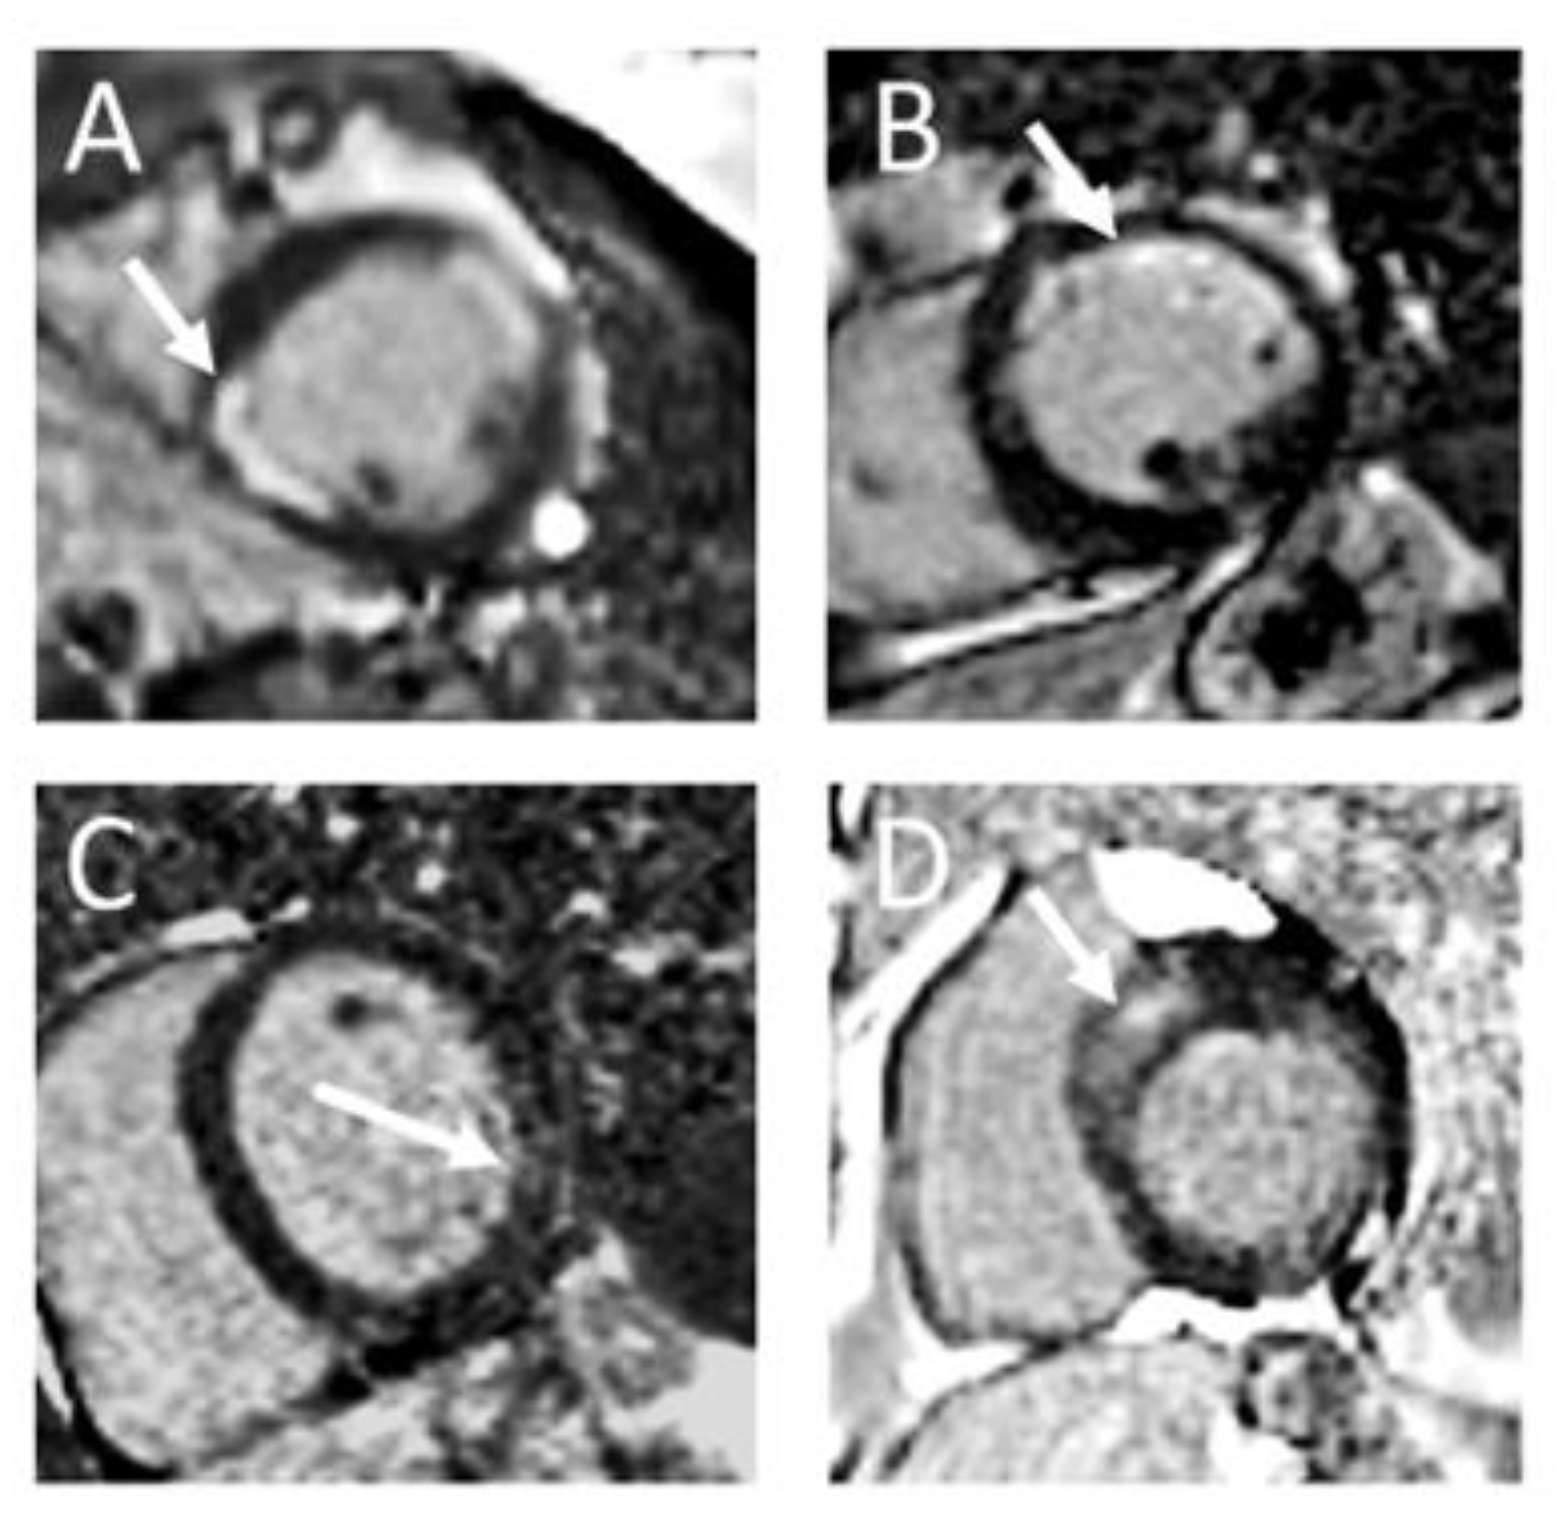

The typical distribution of subendocardial LGE corresponding to a coronary artery territory identifies an ischemic scar, whereby the transmurality indicates the residual vitality [7] (Figure 1A,B and Figure 2A,B). A transmural infarction affects all wall layers from the endocardium to the epicardium, whereas a non-transmural infarction originates from the endocardium and affects <100% of the wall thickness. The size of the infarction, evaluated through LGE-CMR, stands out as the most robust predictor of mortality and significant cardiac events. Not only the infarct transmurality, but also total scar mass, total scar as a percentage of LV volume, gray zone mass, and the peri-infarction-to-core infarction mass ratio are important for risk stratification [8]. So, CMR is also effective in assessing myocardial vitality through discrimination of the LGE extension and segmental kinesis and this can guide coronary revascularization [9]. There is a close relation between the percentage of the left ventricular wall thickness which is affected by the infarction scar and functional recovery after myocardial revascularization: wall segments with <25% LGE extension are more likely to regain contractility than segments with >50% LGE transmurality [10].

Figure 2.

Illustrative examples of LGE in important cardiac diseases: (A): Patient with s/p ST-Elevation myocardial infarctions in anterior and inferolateral location with LGE >50% of myocardial wall thickness. (B): Patient with s/p non-ST-Elevation myocardial infarction in anterior location with subendocardial LGE < 50% of myocardial wall thickness. (C): Patient with viral myocarditis and patchy lateral LGE. (D): Patient with hypertrophic cardiomyopathy (HCM) and septal LGE in the area of greatest hypertrophy.